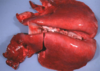

Q

This is a picture of a rumen. What lesion is shown here?

A

Acute, multifocal to coalescing ulcerative ruminitis